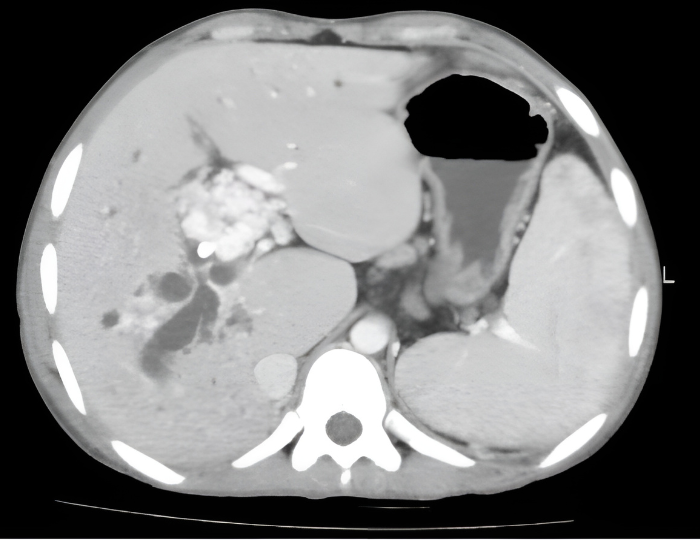

Consequently, even when US findings are suspicious for PMVT, cross-sectional imaging (CT or MRI) with intravenous contrast is needed to confirm the diagnosis. Cross-sectional imaging allows complete evaluation of the portomesenteric venous system as well as identification of porto-systemic collaterals that have implications in procedural interventions and may assist in determining chronicity. Another key benefit to cross-sectional imaging is that it is more sensitive for diagnosis of neoplastic invasion of the portal vein, which has significant management implications. MRI and CT are comparable with respect to evaluation of thrombus, but MRI may offer additional sensitivity in identification of underlying hepatocellular carcinoma.

Figure 2: (A) Depiction of portal venous system with PVT. Note associated collateral vessel dilation (cavernous transformation) in response to sluggish flow in the PV. (B) Axial computed tomographic appearance of portal cavernous transformation with dilated vessels that enhance in portal venous phase.